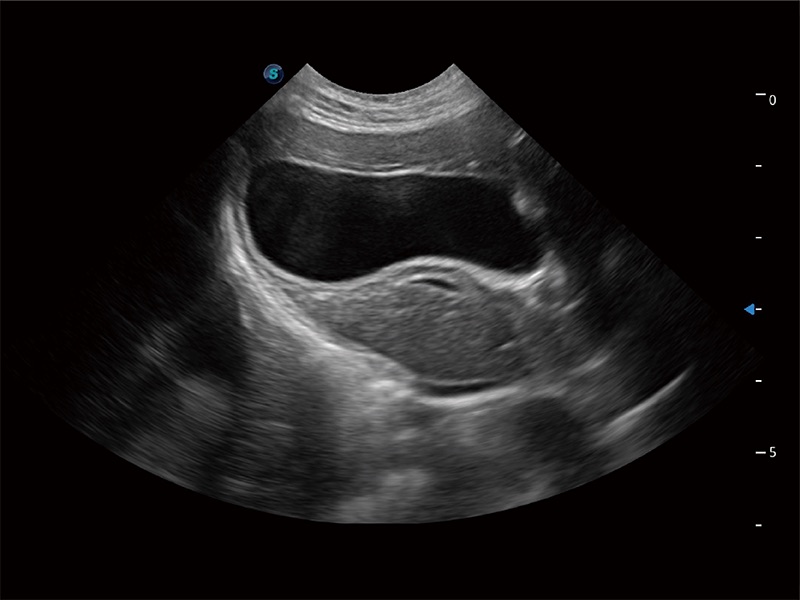

动物是人类最亲密的朋友和最值得信赖的伙伴。玖鼎集团也一直致力于探索动物专用的超声影像解决方案。全新推出的ProPet系列,是玖鼎集团在动物超声影像智能化、专业化、精准化的一次跨越式革新。动物不能用言语来表述自己的不适,通过超声影像,ProPet系列搭建了动物医生与不同物种沟通的“桥梁”,为动物医生注入了“治愈之力”。 ProPet 80 是玖鼎集团匠心打造的一款高端动物专用彩超,采用性能卓越的全新硬件架构,极大提升超声系统的运行效率和数据处理能力,帮助动物医生从容应对日益增多的挑战性病例和日益多样化的临床需求。

高性能和先进的临床应用工具可以为动物医生提供临床信心。ProPet 80 搭载了先进的腹部和浅表应用工具,帮助医生在日常临床实践中发挥前所未有的作用。

一键自动识别膀胱壁及自动测量膀胱容积,不受膀胱形状和大小的限制,帮助医生快速精准获得测量的数据。